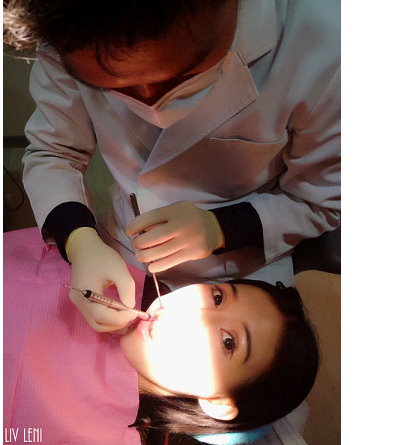

打上麻藥後,開始進行 右邊口腔的牙周刮除術,

雖然看器械好像很可怕,

但因為麻藥的關係,過程中是沒有感覺的,而且相當快速。

(可能也跟病患狀況輕重有關係)

(圖中醫師正拿著牙周探測器,測量我的牙周囊袋。)